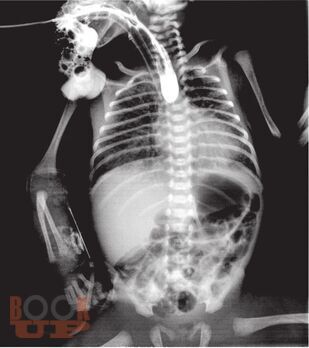

В методическом пособии описаны наиболее распространенные аномалии и пороки развития пищеварительного тракта у детей, а также лучевые методы исследования, с помощью которых диагностируют такие аномалии и пороки.

Пособие иллюстрировано фотографиями оригинальных рентгенограмм и схемами, облегчающими понимание изложенной темы.